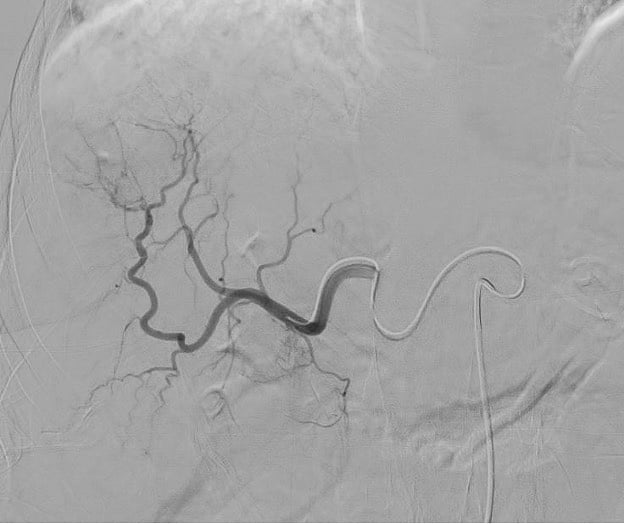

Equipped with sophisticated advanced image-guidance systems and multi-imaging modalities, our physicians may now better visualize and treat patients with complicated diseases. This system includes technology to make this easier in both 2D and 3D with dose reduction technology. It is equipped with integrated Intravascular Ultrasound. Vessel Navigation guidance, 2D Vessel Perfusion, 3D roadmap and Vessel quantitative measurements are offered as well. Vessel Navigator allows reuse of 3D vascular anatomical information from existing CTA and MRA datasets as a 3D roadmap overlay on live X-ray images. With its sophisticated visualization, it provides an intuitive and continuous 3D roadmap to guide you through vasculature during the entire procedure. The system is connected to our PACS system allowing us to visualize previous diagnostic images inside the room.

Stephan Wicky van Doyer, MD: “The performance, technology and quality of the new angio suite is absolutely fantastic. The room size allows multiple providers to feel comfortable and safe. It allows us to perform very challenging procedures in a safe and secure environment for the patient benefit. Different imaging guidance systems such as IVUS and Navigation, shorten the duration of the procedure and our patients also are exposed to a much lower radiation dose.”